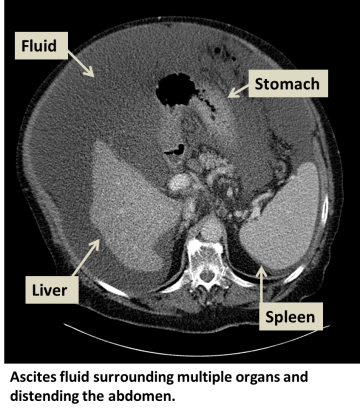

What is ascites?

Ascites is an abnormal accumulation of fluid in the abdominal cavity. Malignant ascites is caused by cancer deposited in the lining of the abdominal cavity.